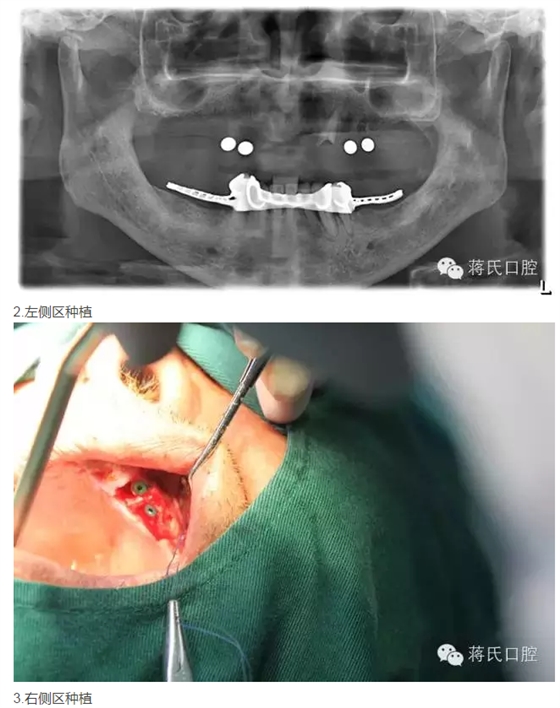

修復(fù)前全景片

3兩側(cè)四五區(qū)種植共4顆

4活動義齒雙重冠修復(fù)

患者情況 男 76歲 ,三類骨。腭咽反應(yīng)重。治療方案 1盡量減少種植費(fèi)用。